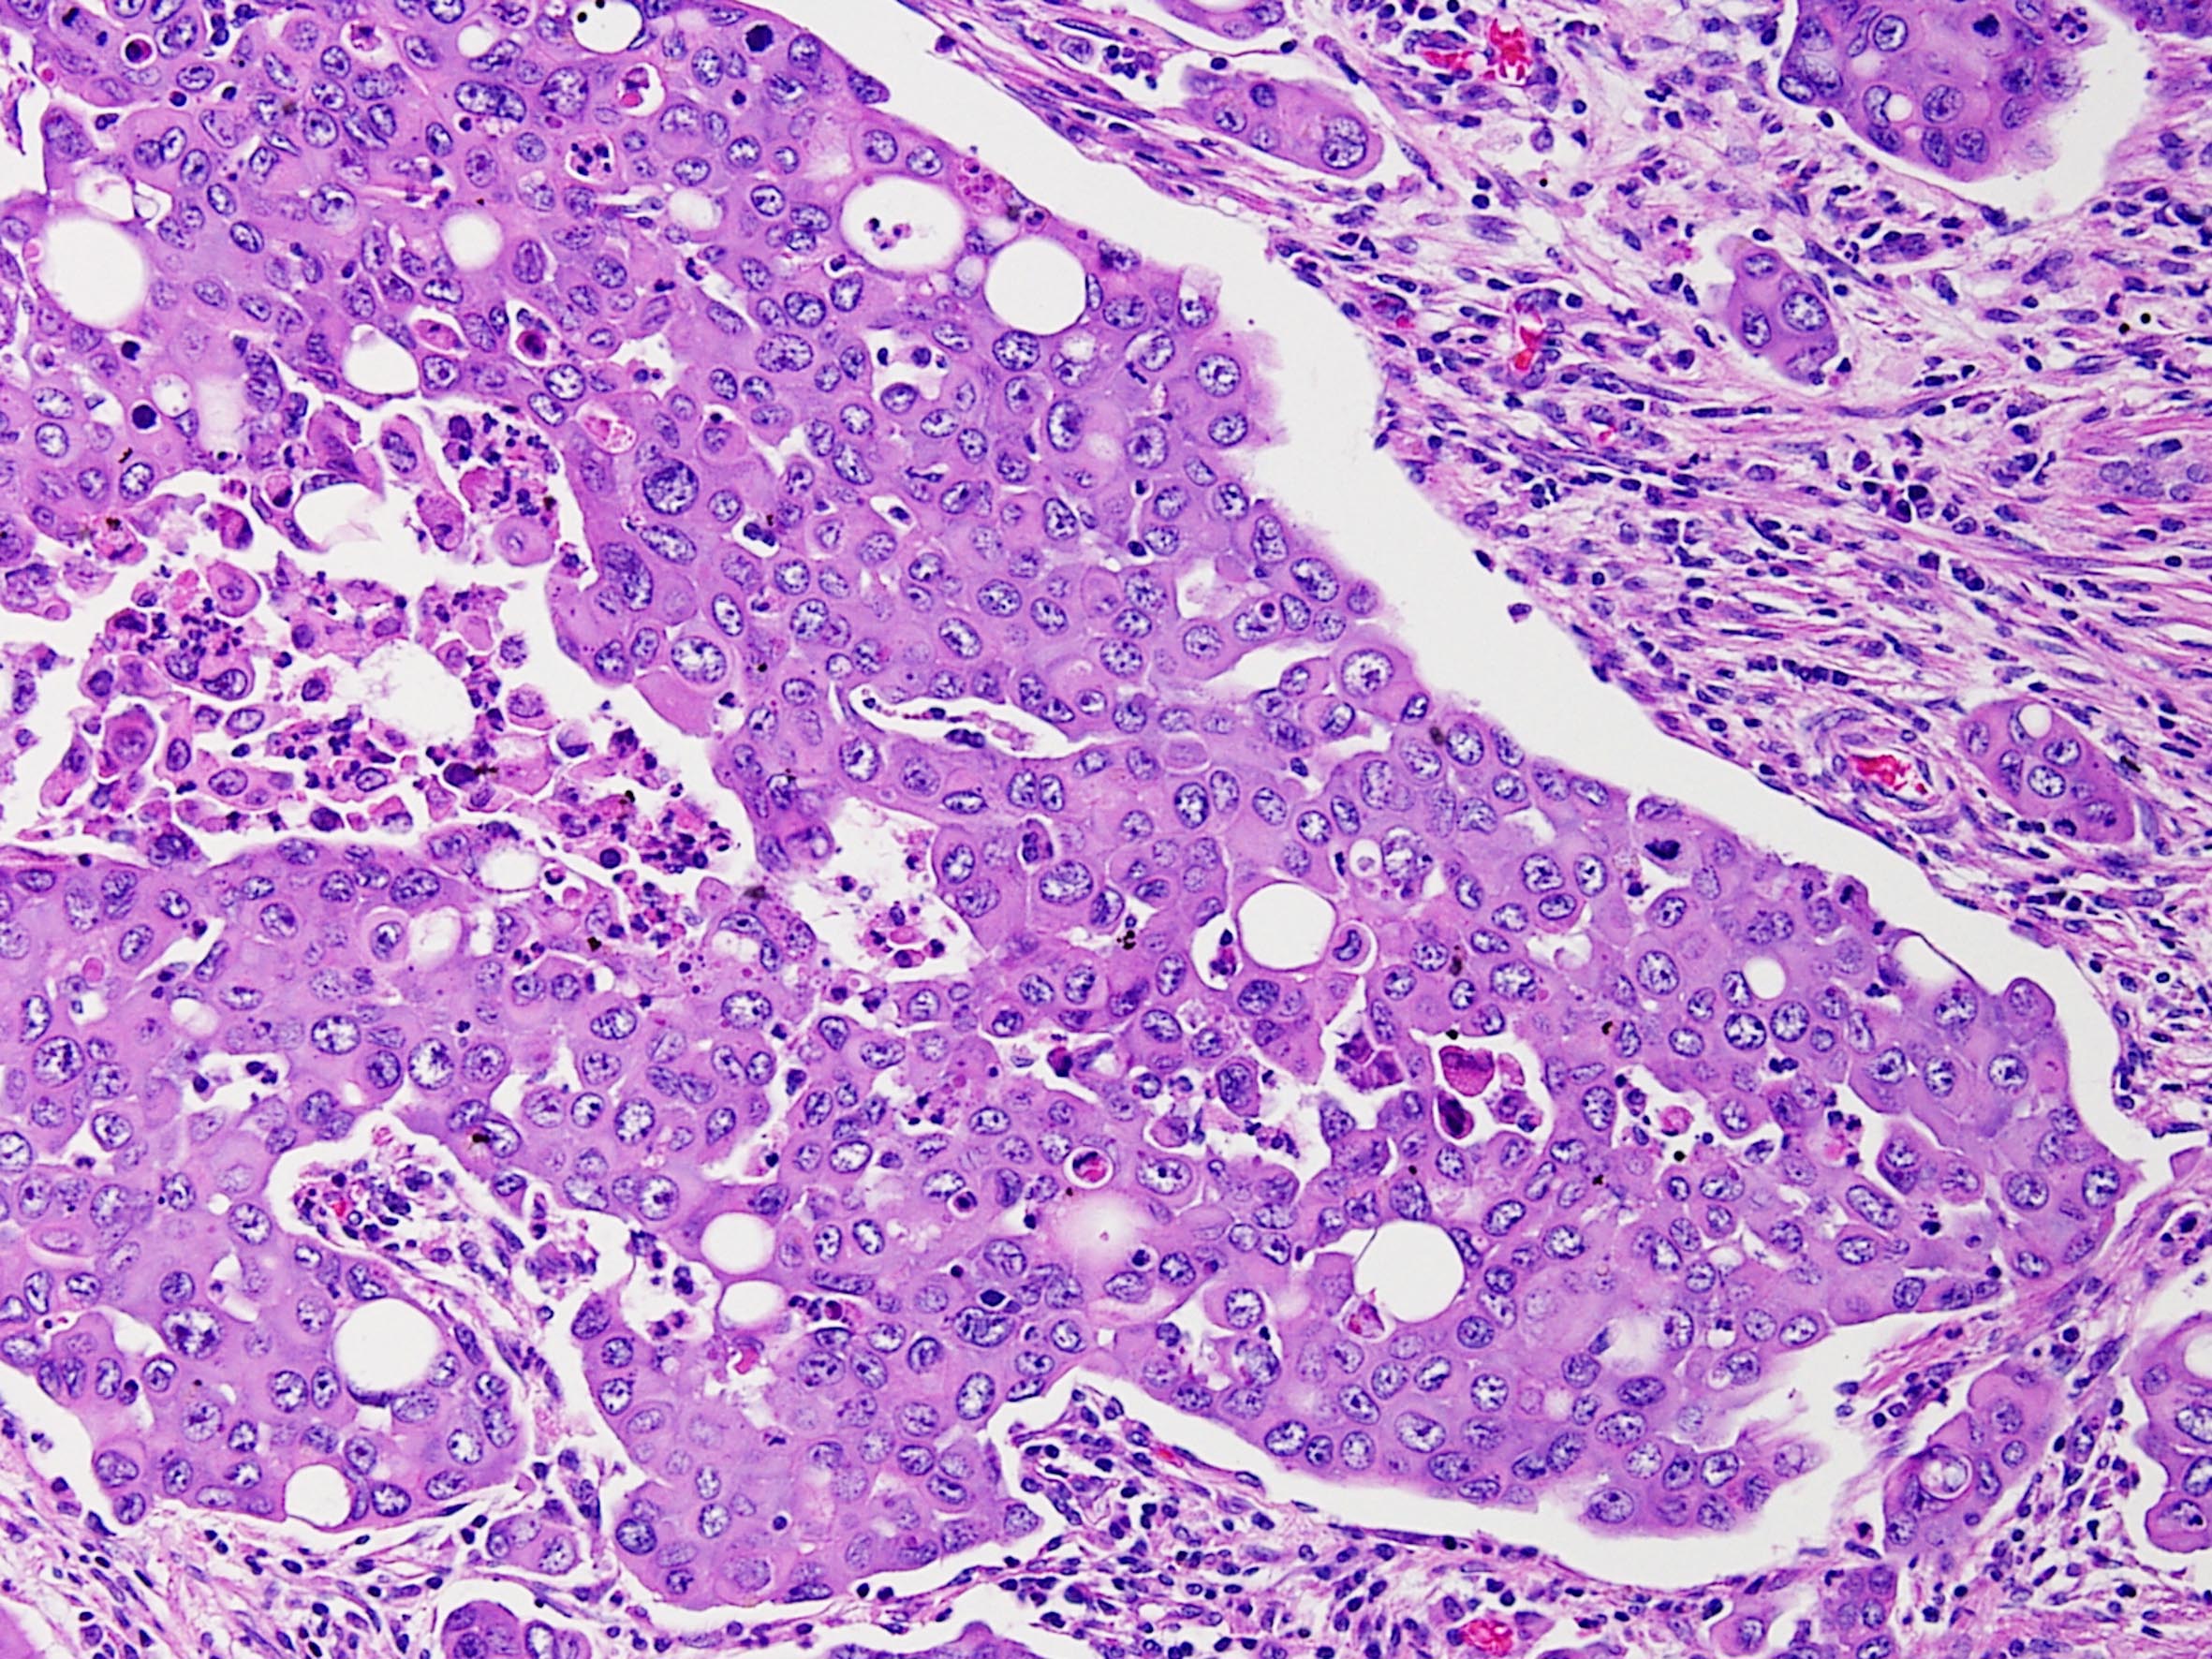

Consensus grade: Renal Medullary carcinoma

Case description (by case creator):

Renal medullary carcinoma